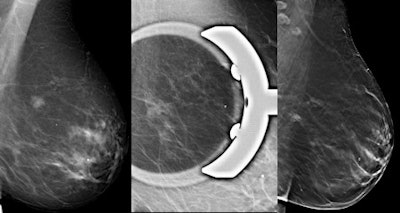

Mammography benefits from a supplementary view with spot compression over suspicious areas to evaluate microcalcifications, opacities, or architectural distortions, or to identify masses. Digital spot compression view (DSCV) is especially useful when a conventional exam results in an equivocal evaluation of findings other than clustered calcifications. With the advent of digital breast tomosynthesis (DBT), 3D cross-sectional visualizations of breast tissue are possible. It has been hypothesized DBT can reduce the recall rate, but that means it must perform as well as or better than DSCV.

According to the hypothesis, a woman with an abnormality requiring DSCV on full-field digital mammography (FFDM) should obtain the same diagnosis as on DBT alone. Dr. Alberto Tagliafico, from the department of experimental medicine at the University of Genoa in Italy, and colleagues compared the two techniques in the same patients to test the hypothesis, and published their findings online first in European Radiology (11 October 2011).

DBT's ability to outperform DSCV may be inherent in its process. The x-ray tube moving along an arc during the examination acquires a 3D volume of the compressed breast, thus the reconstructed breast volume can be explored by scrolling through the slices, allowing the enhancement of the information contained in each plane while blurring the off-focus information.